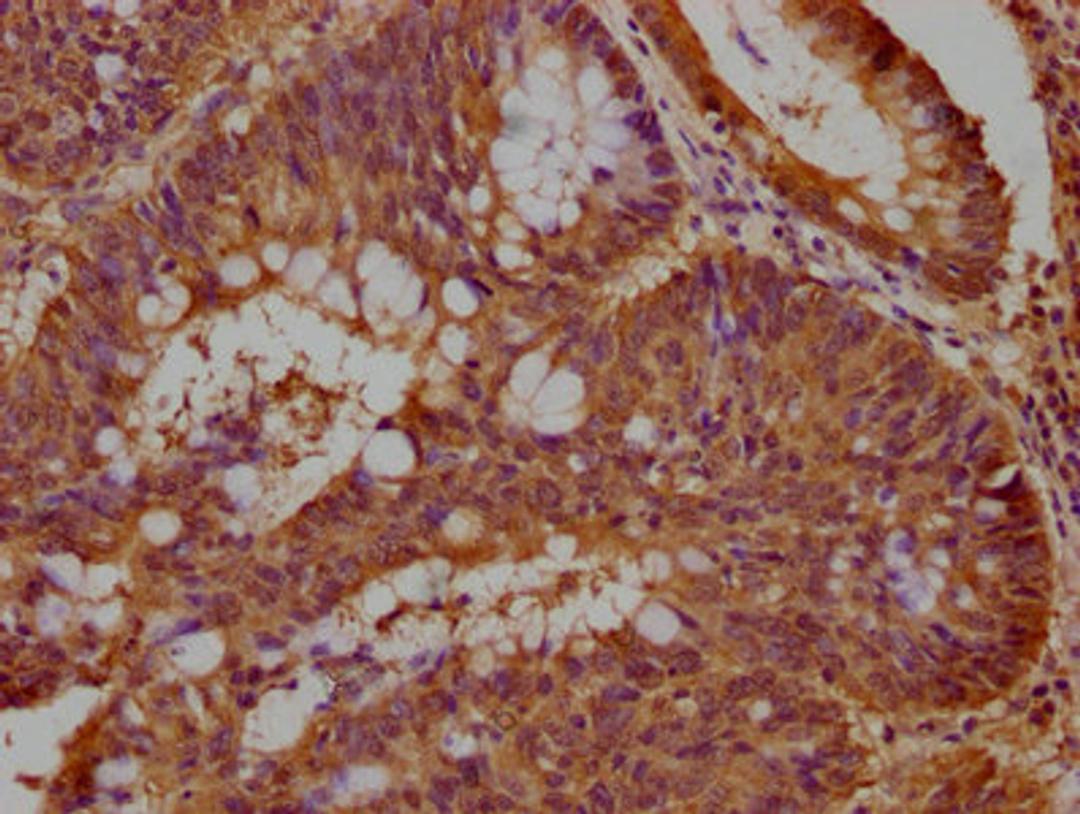

IHC image of CSB-PA850320OA01HU diluted at 1:100 and staining in paraffin-embedded human colon cancer performed on a Leica BondTM system. After dewaxing and hydration, antigen retrieval was mediated by high pressure in a citrate buffer (pH 6.0). Section was blocked with 10% normal goat serum 30min at RT. Then primary antibody (1% BSA) was incubated at 4°C overnight. The primary is detected by a biotinylated secondary antibody and visualized using an HRP conjugated SP system.